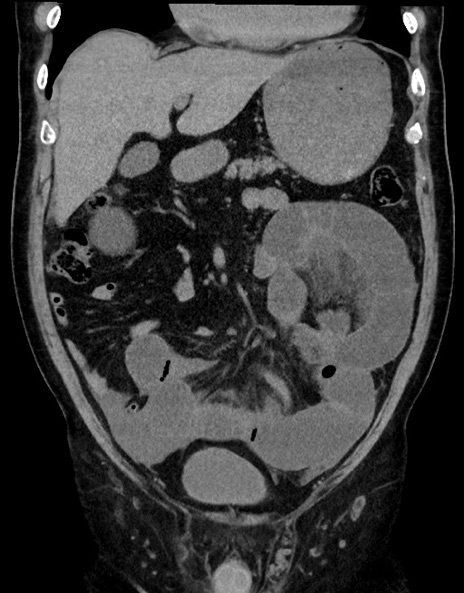

症例15(冠状断像)

【症例】70歳代男性

【主訴】腹痛

【現病歴】今朝から腹痛あり。全体的に痛い。特に左上の方。排ガスが今日はない。冷や汗が出る。

【既往歴】直腸癌術後

【身体所見】左側腹部〜上腹部に圧痛あり。腹膜刺激症状明らかなではない。軽度反跳痛。左下腹部に術後瘢痕あり。

【データ】WBC 7700、CRP 0.02